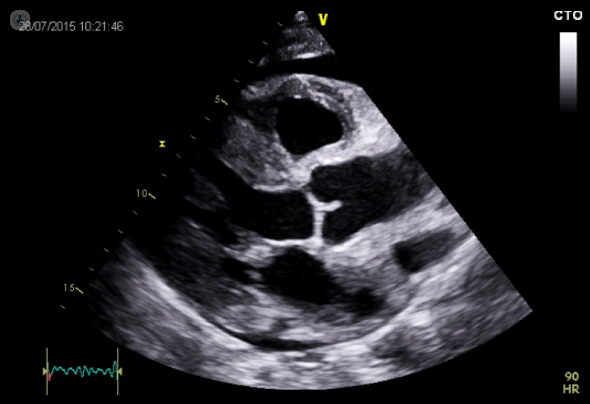

Welcome to our Echocardiography learning platform, where we are aim to help you learn & develop your echocardiography skills from home.